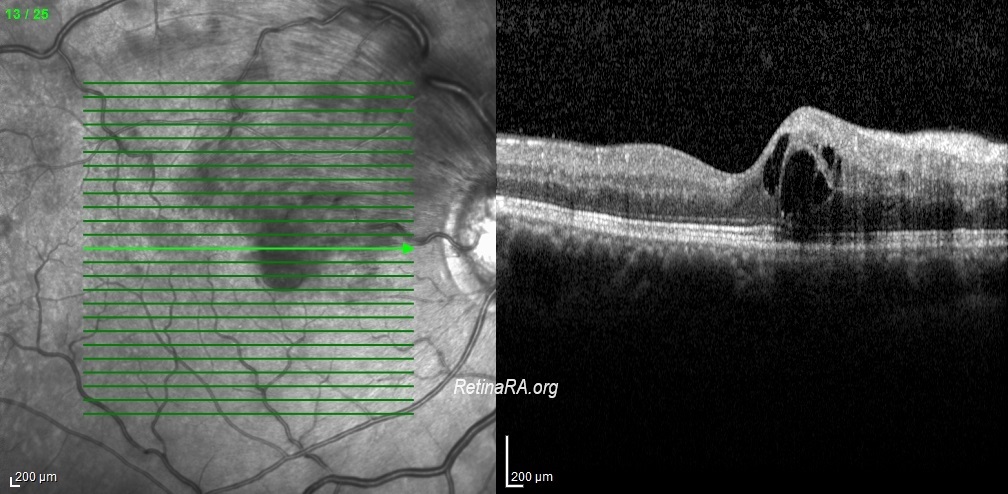

Hemi-CRVO has been shown to be a distinct entity that is clinically and pathogenetically closely related to CRVO and unrelated to BRVO due to fundamental differences between the two. Hemi-CRVO clinically presents as either venous stasis retinopathy or as hemorrhagic retinopathy, usually involving one half of the retina, although occasionally it may involve one third to two thirds of the retina. The clinical features of venous stasis retinopathy and hemorrhagic retinopathy caused by hemi-CRVO are identical to those caused by CRVO. Visual prognosis seems to be better in hemi-CRVO than in total CRVO.

Credit: Kemal Tekin, M.D., from Ulucanlar Eye Training and Research Hospital